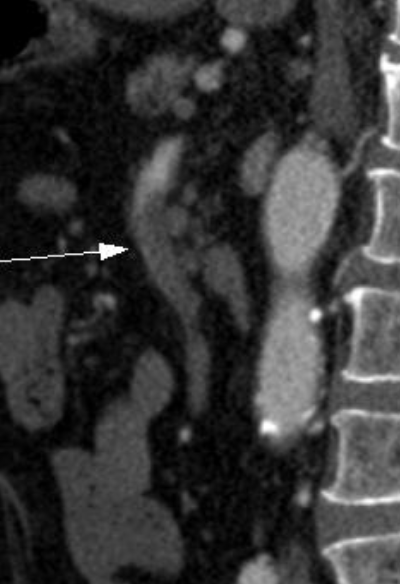

#. SMA dissection

박리된 혈관의 모습, 찢어진 동맥 혈관층 사이로 피가 조금씩 밀려 들어가 동맥혈관층 사이가 갈라지며 false lumen이 형성된다. false lumen은 피가 들어가는 입구는 있으나, 나오는 출구가 없어 내부 압력이 증가하여 박리의 범위가 늘어나게 되고, 오히려 true lumen의 혈류를 방해하는 결과를 초래하게 된다.

실제 환자의 CT angiography 영상.

빨간색 화살표는 true lumen을 가리키고, 노란색 화살표는 SMA dissection으로 형성된 false lumen을 가리킨다.